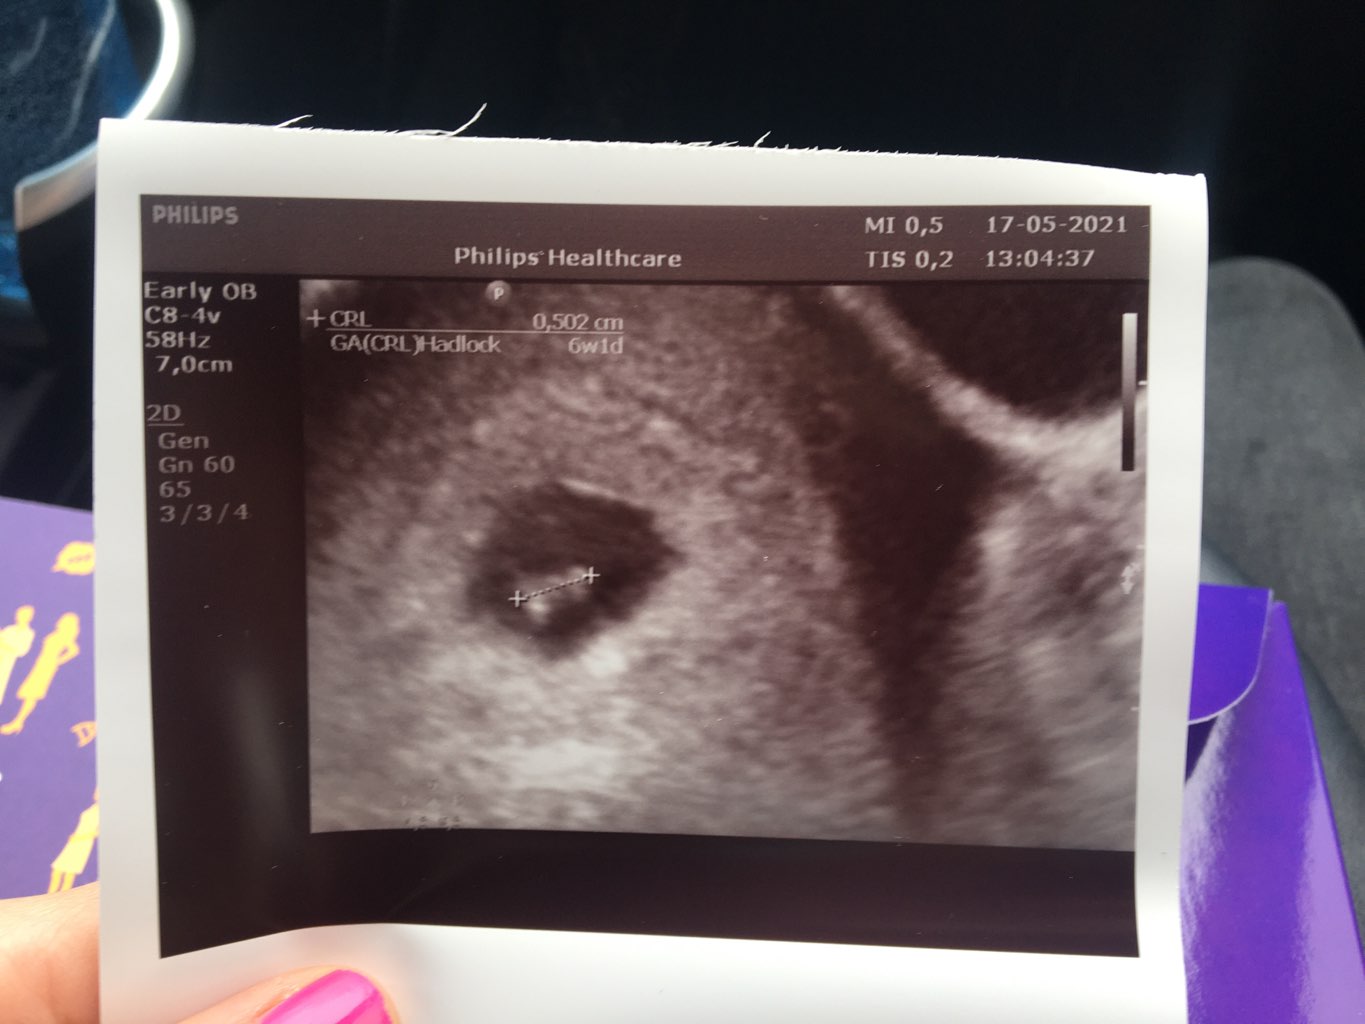

6dni minęło jak 1 dzień bo pokazuje 6+1 a we wtorek było 6. Wg OM dziś to 7+0. Wszystko w porządku jest fasolka i serce bije 😍 książeczkę ciąży dostałam i wszystkie badania zlecone na 01.06 następna wizyta 🥰

nie wiem sama tez 🤔 ja już mam w aplikacji zaczęty 8 a ta mi mówi ze 6 (zaczety7) No dziwne ale ważne ze wszystko dobrze. Z tego tygodnia obliczyła mi 27.12 😱